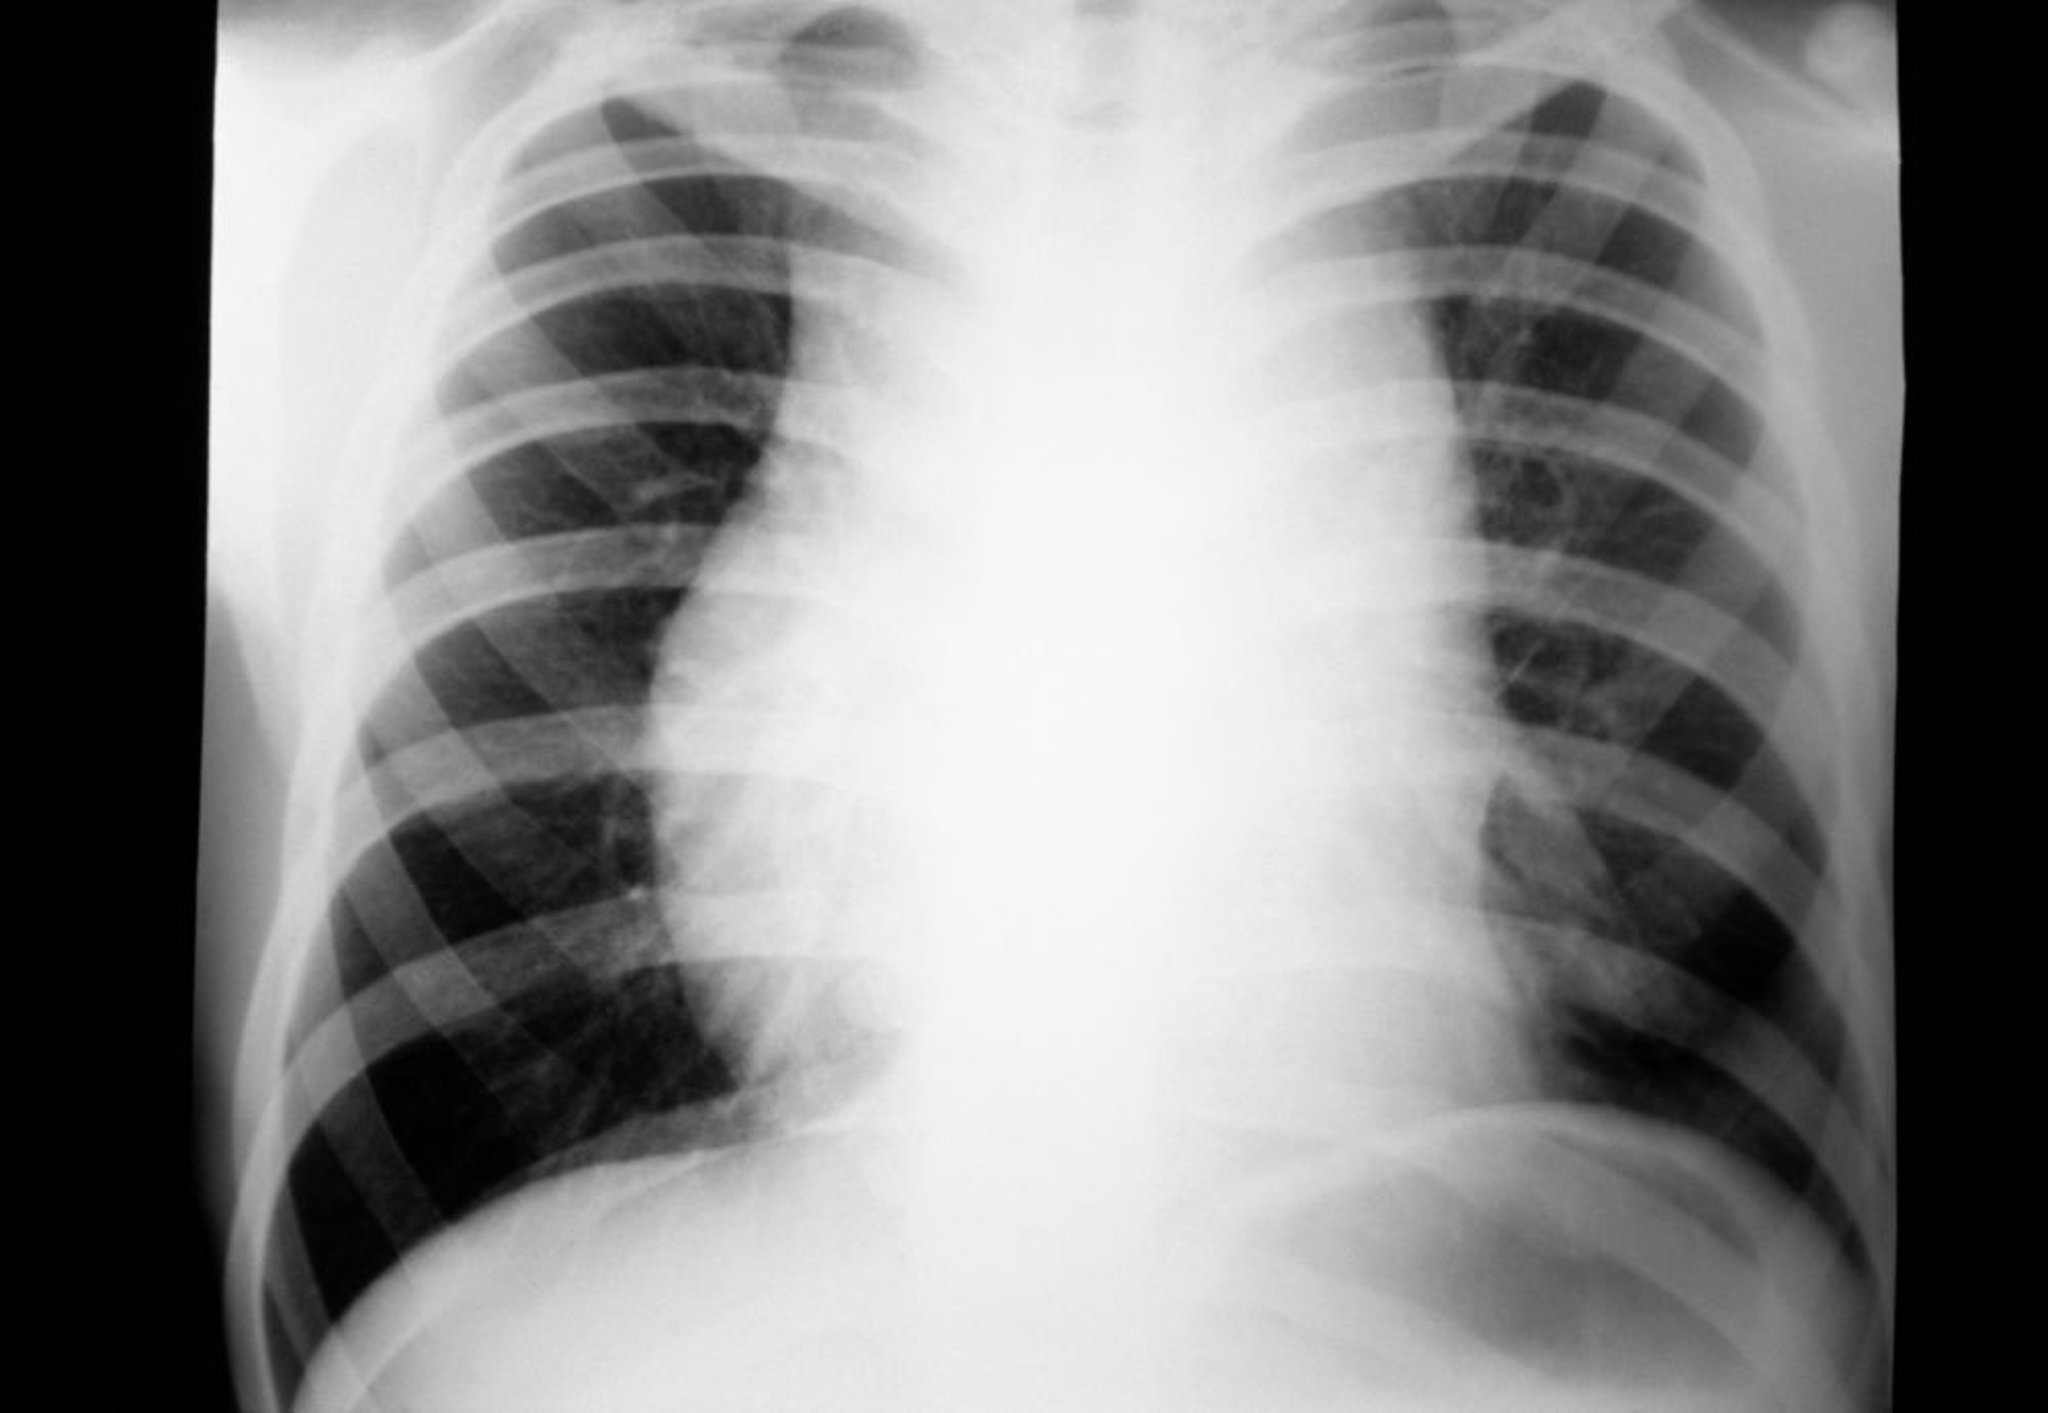

Hodgkin Lymphoma (Mediastinal Lymphadenopathy)

Chest radiograph of a patient with Hodgkin lymphoma showing mediastinal lymphadenopathy.